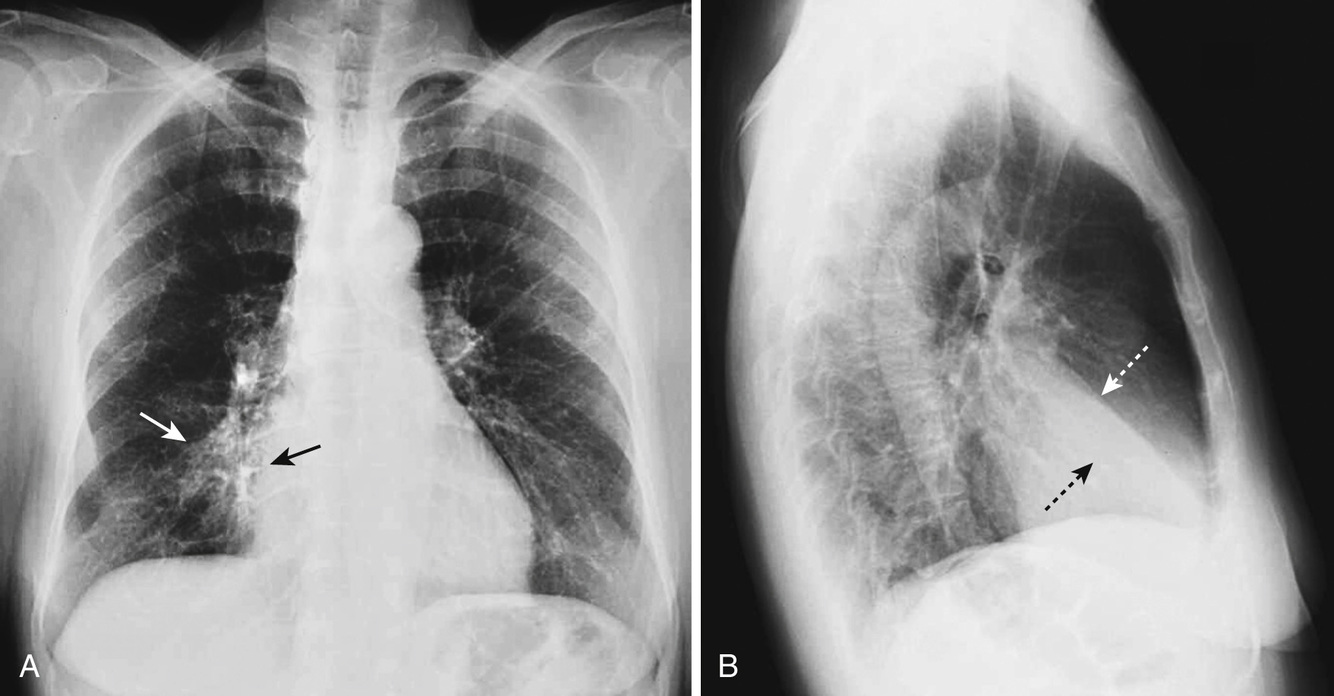

What is going on in this radiograph?

Left atrial enlargement

The potential space over where the left ventricle sits is where the atrium will expand into. You can also tell by the upward deviation of the carina, and the obtuse carinal angle